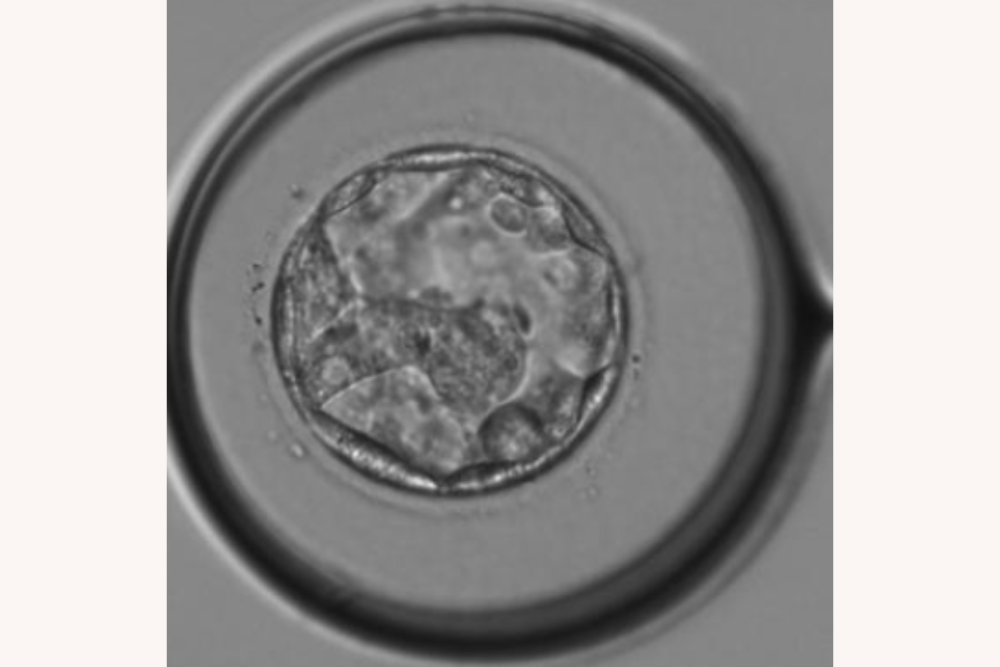

2つできた胚盤胞のうち、体外受精のほうが4AB、顕微授精のほうが3CCというグレードで、4ABの胚盤胞を移植して妊娠することができました。

体外受精にステップアップしてよかったことは、受精の時点から細胞分裂して成長していく過程を見ることができたこと。移植のときもモニターで胚盤胞が子宮に入る様子を見せてもらい、感動しました。

体外受精をしたから見ることができた、受精卵。